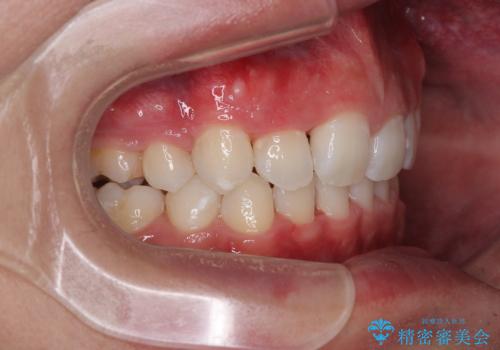

- 「前歯のデコボコが気になる」「前歯の中心がずれていて気になる」とご相談に来られた患者様の症例です。

診察の結果、上下の歯が並ぶためのスペースが不足しており、特に上顎右側の側切歯が内側(口蓋側)に転移していたため、正中が大きく右にずれている状態でした。